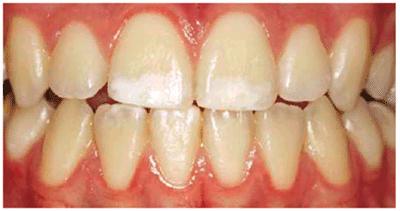

either on an individual tooth or on all teeth (Figures 16-1A, and 16-1B). There are many causes and

Figure 16-1A: An otherwise attractive smile is marred by discolored teeth.

Figure 16-1B: After tooth lightening, the smile is much more pleasing.